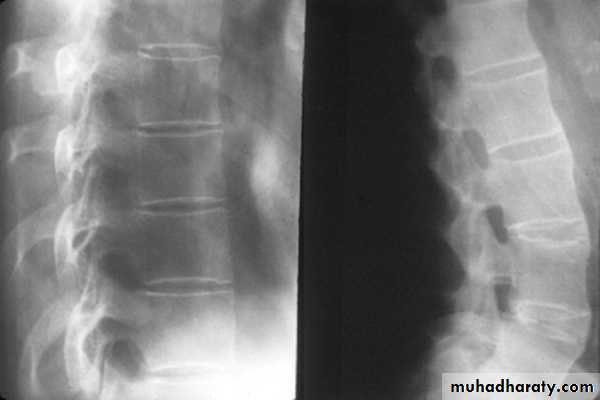

X-rays of the sacroiliac joint show irregularity and loss of cortical margins, widening of the joint space and subsequently sclerosis, joint space narrowing and fusion.Lateral thoracolumbar spine X-rays may show anterior ‘squaring’ of vertebrae due to erosion and sclerosis of the anterior corners and periostitis of the waist.

Bridging syndesmophytes may also be seen, which are areas of calcification that follow the outermost fibres of the annulus.

In advanced disease, ossification of the anterior longitudinal ligament and facet joint fusion may also be visible. The combination of these features may result in the typical ‘bamboo’ spine.

‘Bamboo’ spine of advanced ankylosing spondylitis. Note the symmetrical marginal syndesmophytes (arrows), sacroiliac joint fusion and generalised osteopenia